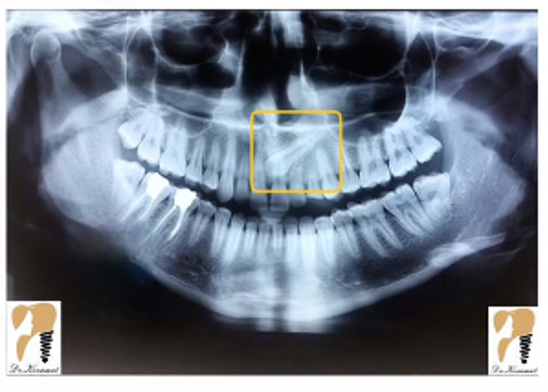

برای تشخیص نهفتگی دندان متخصص شما را به انجام عکسبرداری و رادیوگرافی ارجاع می دهد. یک رادیوگرافی OPG حتما مورد نیاز است. در بعضی موارد برای تشخیص دقیق محل دندان نیاز به رادیوگرافی تکمیلی از جمله رادیوگرافی اکلوزال, لترال سفالومتری و یا CBCT می باشد.

اگر رادیوگرافی OPG تهیه کردید و با چنین تصویری مواجه شدید حتما از یک متخصص جراح فک و صورت کمک بگیرید.